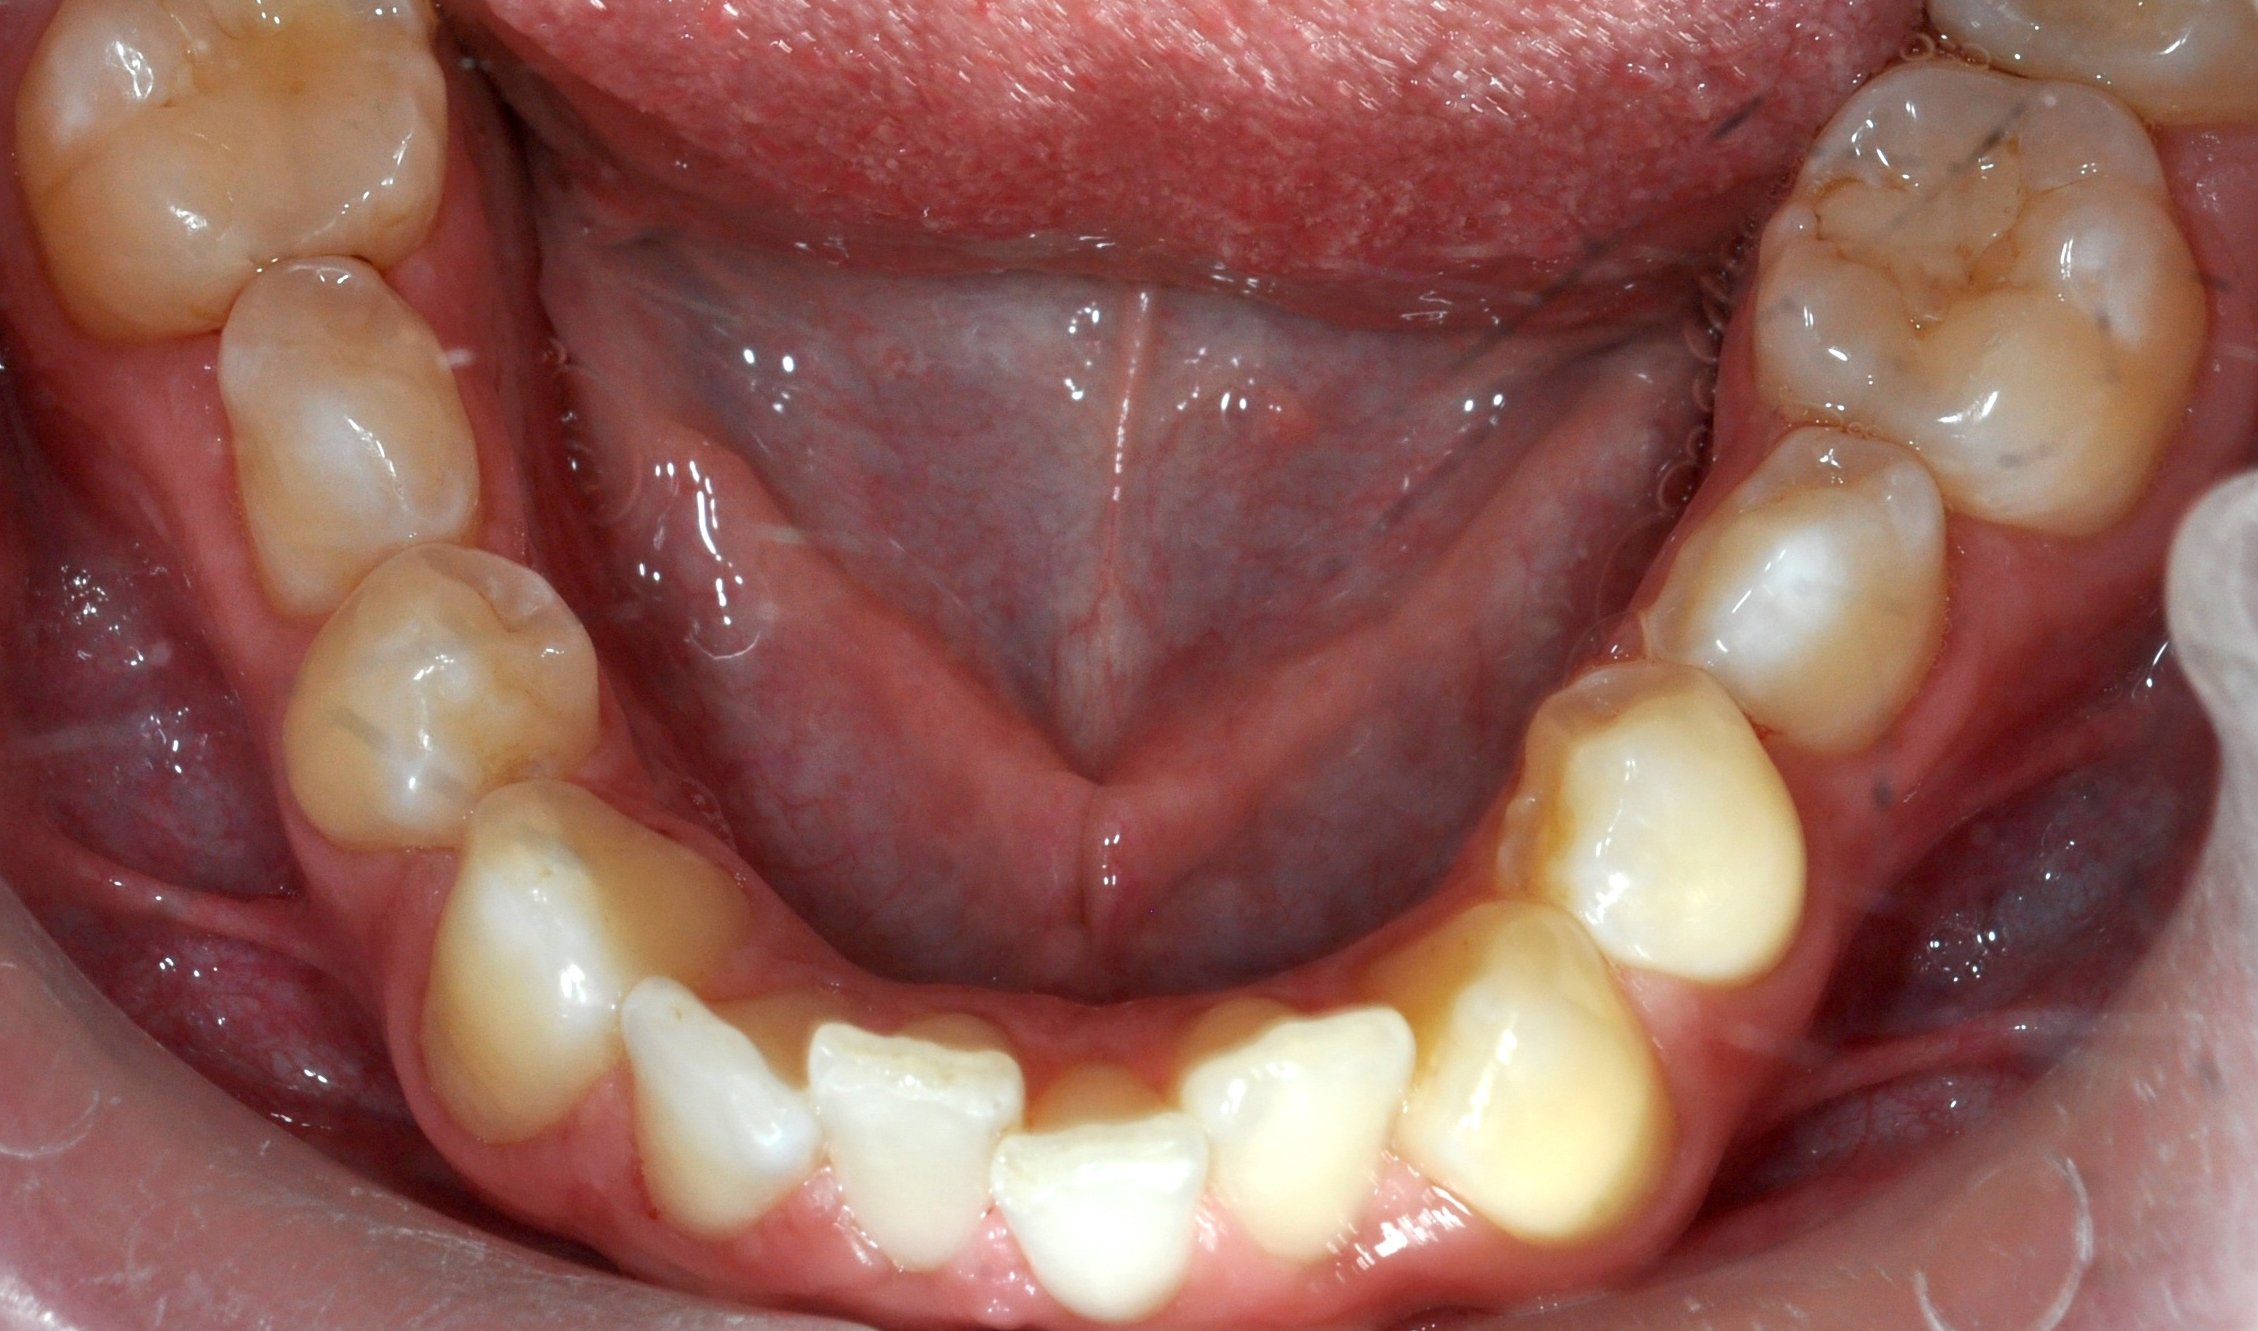

Paziente adulto con importante affollamento dei denti inferiori, arcate strette e tendenza al morso aperto, con difficoltà nel corretto contatto tra i denti superiori e inferiori.

Il trattamento con allineatori trasparenti ha permesso, in circa 18–20 mesi, di riallineare i denti, ampliare le arcate e migliorare la chiusura del morso, ottenendo un risultato stabile, funzionale ed esteticamente armonioso.

DOPO